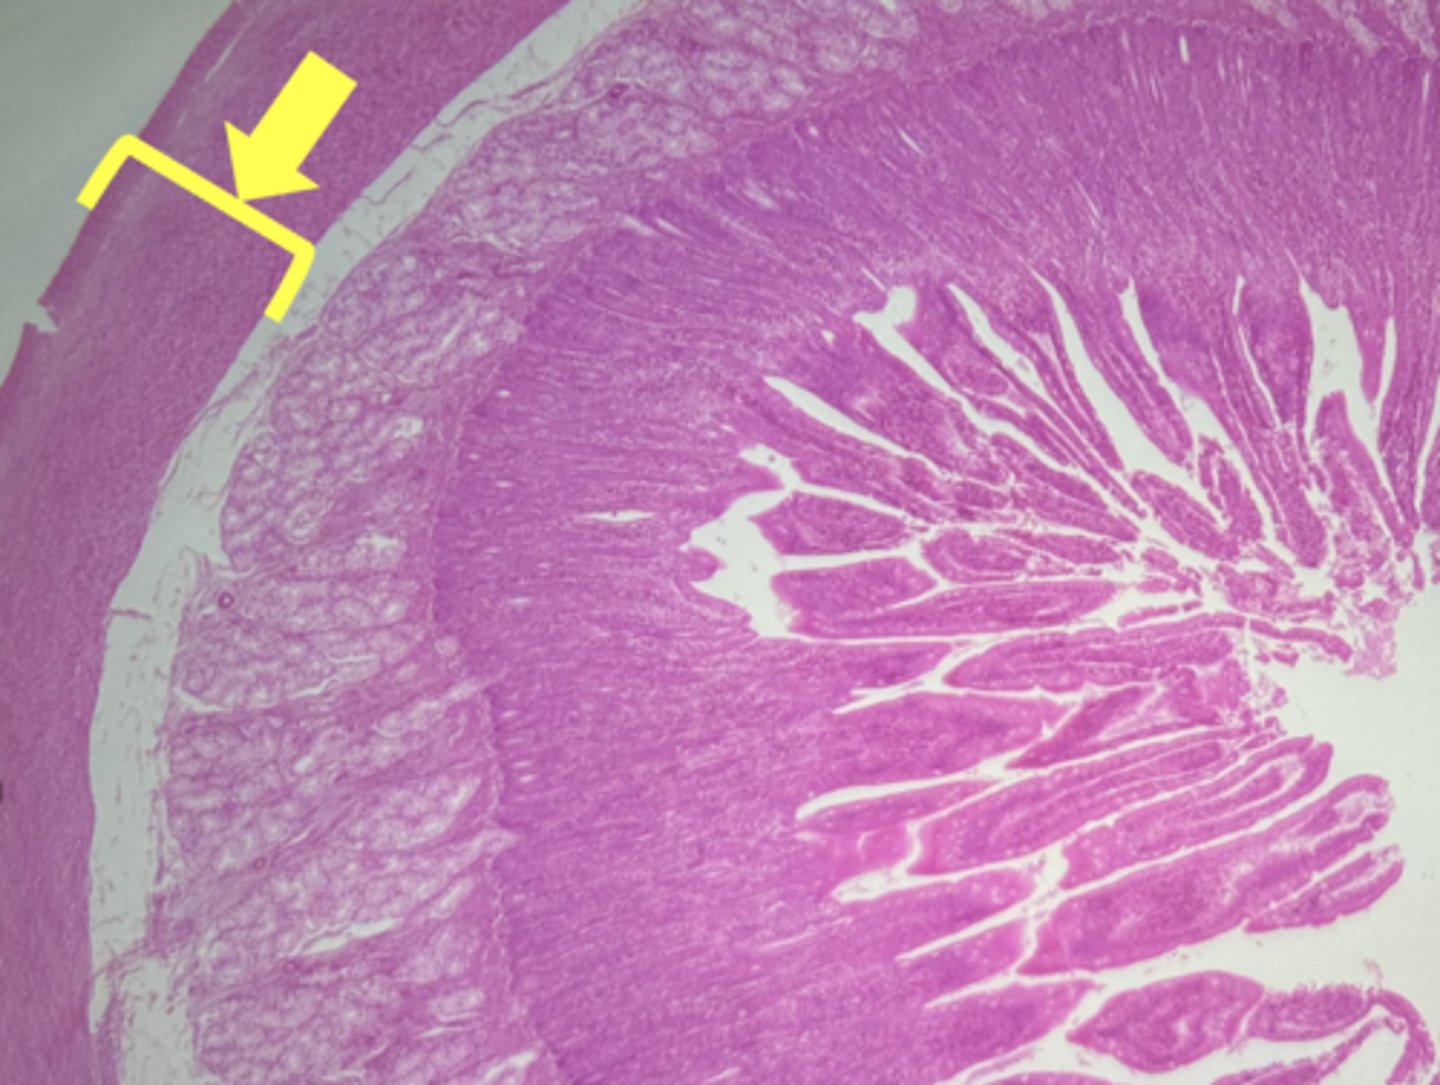

Esophagus

name the tissue

Mucosa

(esophagus)

Submucosa

muscularis externa

stratified squamous epithilium (KEY CHARACTERISTIC)

lamina propria

muscularis mucosae

circular layer

longitudinal layer

A- Esophagus

B- Stomach

Name the Tissue A & B